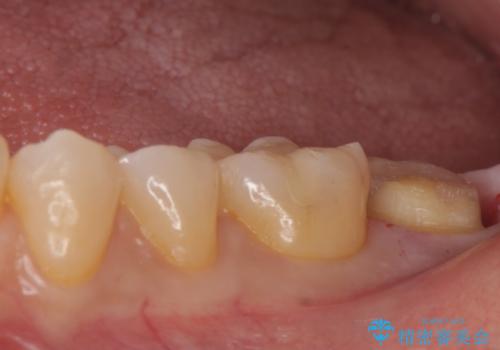

白い物で治療して欲しいとのことで、セラミックの詰め物だと詰め物の範囲が大きく、割れてしまう可能性があるので

ジルコニアクラウン(被せもの)で治療を行いました。

- 仮歯・ジルコニアクラウン 12.1万円費用は治療当時の料金となります